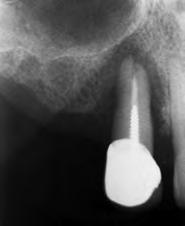

Presentamos el caso de un paciente varón de 57 años que acude a la consulta demandando tratamiento dental para sustituir sus prótesis removibles superiores por una rehabilitación implantosoportada. Presenta un esquelético superior que se sustenta sobre los caninos (13 y 23), existiendo movilidad en la pieza 13 y dolor. En las imágenes iniciales podemos observar el estado de desajuste en el que se encuentra el esquelético y la afectación de la pieza 13 donde se objetiva una recesión que deja al descubierto parte de la raíz dental (Figura 1-4). En la radiografía panorámica inicial se observa un defecto circunferencial grave en el canino superior derecho y una neumatización excesiva de ambos senos

maxilares, lo que apunta a la existencia de una atrofia vertical ósea excesiva en esta área que pretende ser rehabilitada con implantes dentales (Figura 5). A mayor aumento vemos la fractura radicular de la pieza 13 que ha generado el defecto circunferencial (Figura 6) y en el cone beam de planificación se constata y además se pone de manifiesto la dimensión del defecto óseo y el volumen óseo residual a nivel palatino de 2 mm (Figura 7).

Figura 5. Radiografía inicial del paciente. En ella observamos el defecto crateriforme del diente 13 y una neumatización excesiva de ambos senos maxilares en el maxilar posterior donde se pretenden realizar implantes dentales. Figura 6. Imagen en detalle de la pieza 13. En esta imagen cercana podemos observar una fractura vertical evidente en el área del ápice ya en este tipo de prueba radiológica. Figura 7. En el cone-beam de planificación se objetiva la fractura y el defecto crateriforme con pérdida de la tabla vestibular completa y un remanente óseo a nivel palatino de 2 mm para la posterior inserción de un nuevo implante.